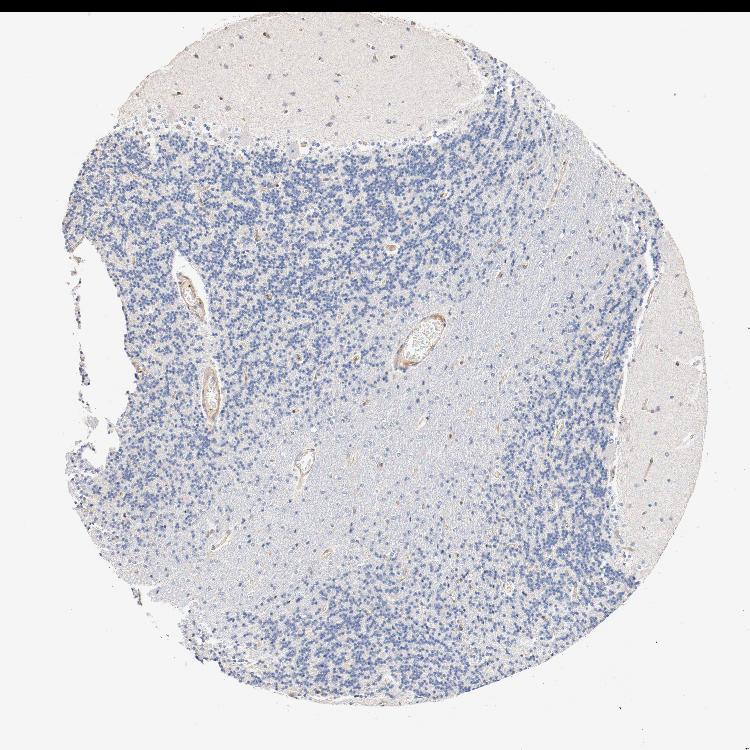

CEREBELLUM - Antibody stainingi

Antibody staining in the annotated cell types in the current human tissue is reported as not detected, low, medium, or high, based on conventional immunohistochemistry profiling in selected tissues. This score is based on the combination of the staining intensity and fraction of stained cells.

Each image is clickable and will lead to virtual microscopy that enables deeper exploration of all samples and also displays staining intensity scores, fraction scores and subcellular localization as well as patient and tissue information for each sample.

Antibody CAB004041

Purkinje cells Not detected

Cells in granular layer Not detected

Cells in molecular layer Not detected